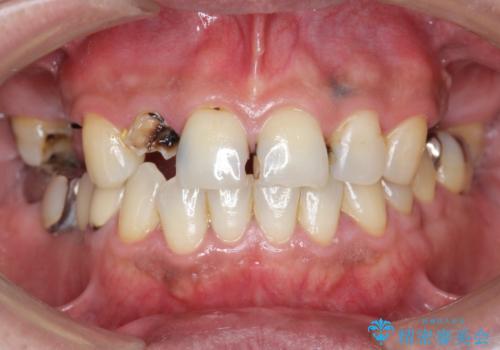

「 放置した虫歯 」 前歯セラミック治療

- 前歯の虫歯に気付きながらも放置し、一念発起し治療を希望され来院されました。

虫歯のマイクロスコープによる丁寧な除去、根管治療、深い虫歯に対する挺出(エクストリュージョン)および歯周外科を行ったのち精度の高いセラミッククラウン製作治療を計画します。

虫歯の放置により、根管治療や深い虫歯に対する処置が必要になりましたが丁寧に一つづつ処置を行ったことで抜歯をすることなく歯を残すことができました。